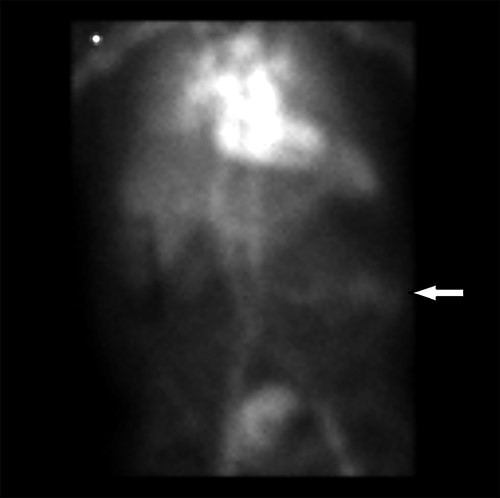

At the time of his PET scan, the patient acutely developed diffuse abdominal pain and vomiting. The scan was aborted and the patient was rushed to the emergency department. An abdominal X-ray and a CT scan of the abdomen and pelvis showed small bowel dilatation, but there was no intestinal mass lesion (Fig. 1). He was placed on nasogastric tube decompression. The patient reported having melena that morning. The hemoglobin was found to be 6.1 g/dl and a tagged RBC nuclear scan showed active gastrointestinal bleeding (Fig. 2) at the approximate location of the transition zone of the small bowel obstruction seen on CT.

Radionuclide RBC scan showing active hemorrhage within the mid-small intestine (arrow).

Melanoma is known to metastasize hematologically to the small intestine and should be highly suspected in patients who develop gastrointestinal symptoms [4, 10]. Since our patient did not have prior melanoma, he underwent a prolonged evaluation with multiple admissions until urgent surgery was ultimately indicated for hemorrhage and small bowel obstruction. Melanoma in the small intestine leads to gastrointestinal hemorrhage due to erosion of the intestinal mucosa [11]. Signs of hemorrhage range from chronic iron deficiency anemia, hemoccult positivity on rectal examination or melena. Evaluation for the source of gastrointestinal hemorrhage commonly consists of upper endoscopy and colonoscopy, however, they are limited from diagnosing jejunal or ileal tumors [12]. CT with arteriography may reveal active hemorrhage. After the CT arteriography showed no hemorrhage, intussusception or mass lesion, our patient underwent a tagged RBC radionuclide scan, which showed hemorrhage into the small intestine.